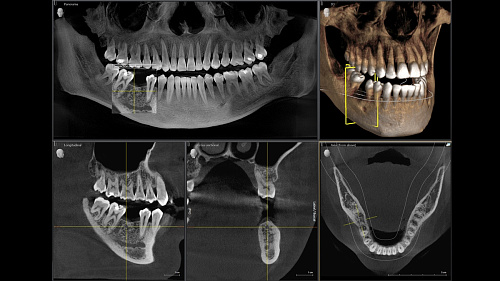

Диагностика последнего поколения, идеально решающая задачи рентгеновского обследования независимо от размеров клиники. Поля изображения зависят от определенной клинической картины, поэтому специалистам так удобно работать с ORTHOPHOS SL 3D. Данная установка делает объёмные картинки для одиночной реставрации в 3D качестве полностью всей челюсти такого размера, которого требуется.

Датчик DCS служит для выставления резкости снимков, причём его технологические особенности можно считать революционными для современного рынка стоматологического оборудования.

ОБЪЁМ ДЛЯ ЛЮБЫХ ЦЕЛЕЙ

Планирование одиночной реставрации, эндодонтические исследования и пр. – для этого специалист может выбрать объёмные варианты 8 х 8 см или 11 х 10 см, также предлагается объём 5 х 5,5 см. Снимки в HD-качестве, стандартные настройки или выбор объёма обследования в зависимости от диагноза — всё это врач получает в отличном качестве, а для пациента излучение в районе исследования минимально.

Датчик прямого преобразования DCS

Конструктивные особенности датчика DCS заключаются в превращении рентгеновского излучения в электрическую энергию. Обычная для таких случаев промежуточная стадия светового луча отсутствует. Другими словами, значительно снизив потери сигнала, производитель максимально улучшил чёткость.

С технологией SL можно за один сеанс получить огромное количество снимков. Те из них, где фокусировка наиболее чёткая, автоматически соединяются. В итоге одна процедура — снимки челюсти полностью в самом лучшем качестве. Даже нестандартные случаи не станут помехой в обследовании. К примеру, при ретинированных зубах уже после того, как снимок сделан, нужную область можно выделить подробнее, и в ещё одном рентгене необходимость отпадает.